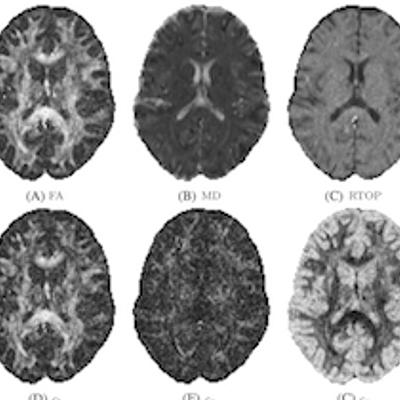

Thomas Schultz and Anna Vilanova

Diffusion MRI visualization

2018

pdf

more